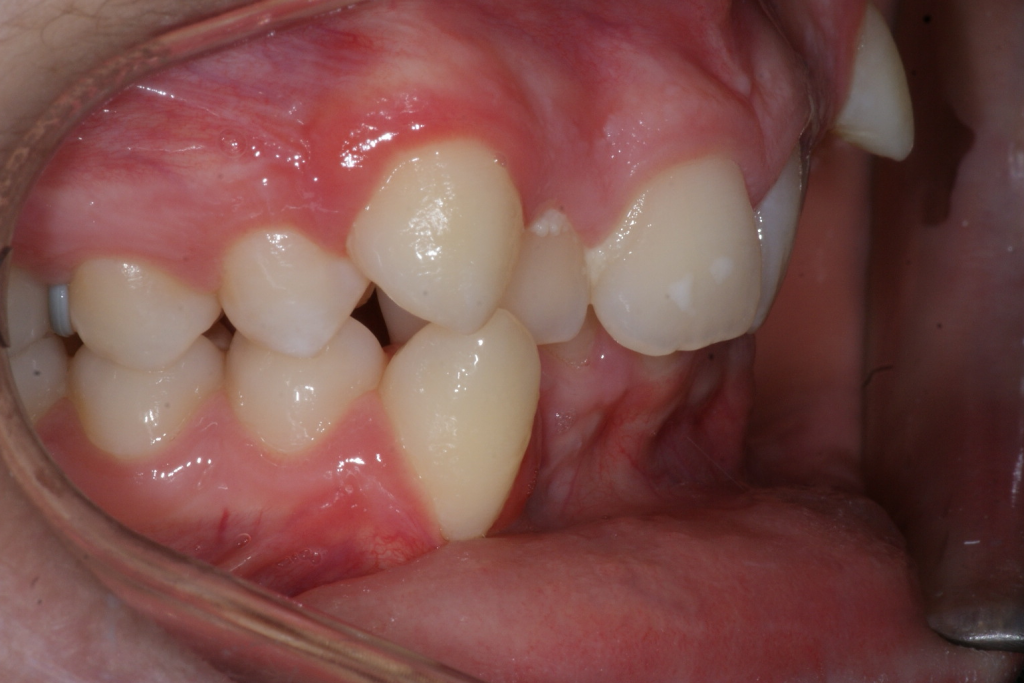

Correction d’une malocclusion de type Classe II avec chevauchement sévère aux 2 arcades. Des appareils fixes (boîtiers), une expansion palatine et l’extraction de 4 prémolaires (#14-24-35-45) furent nécessaires pour améliorer ce sourire. Traitement chez un adolescent, réalisé en 28 mois.